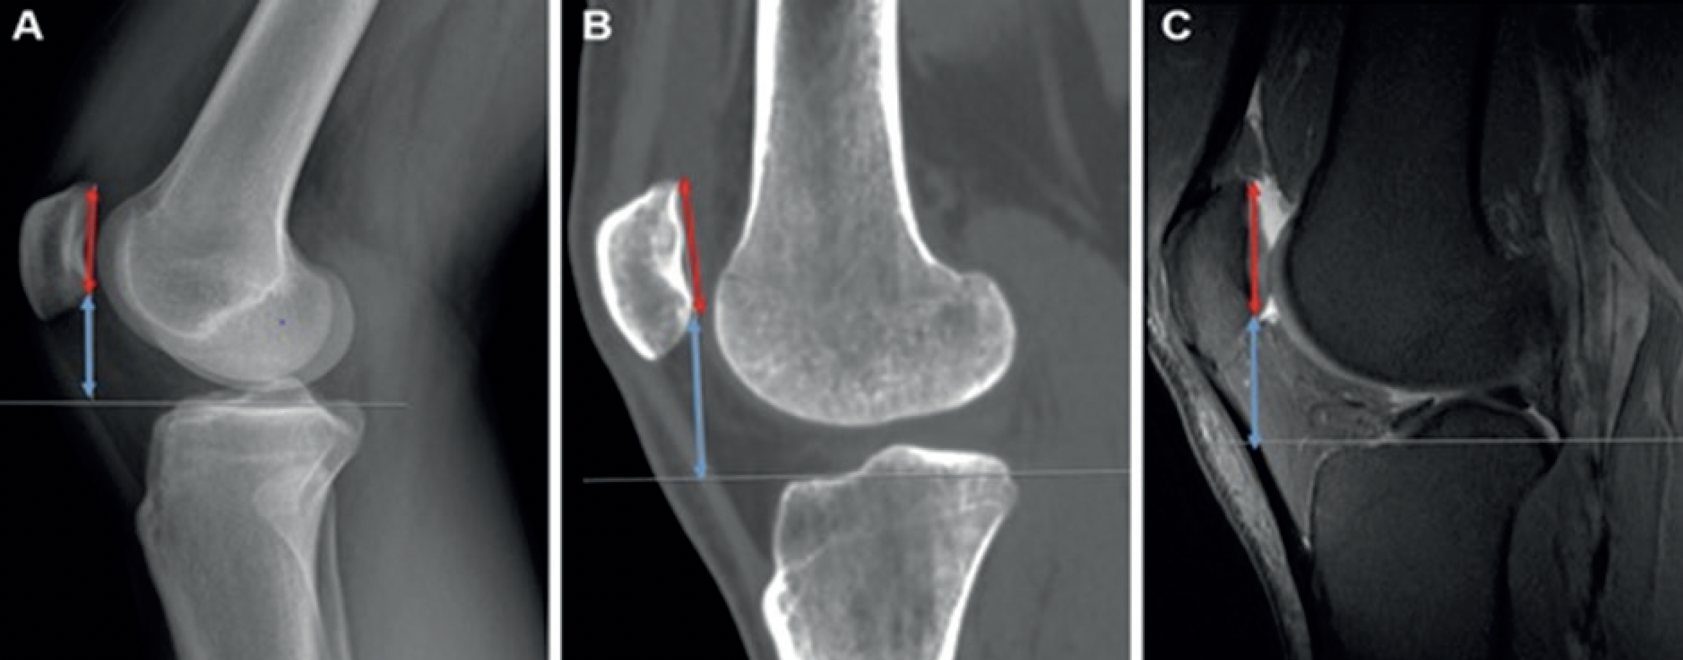

For the Blackburne–Peel (BP) method (Figure 1), the length of the patellar articular surface and the perpendicular distance from its inferior margin to the medial tibial plateau were measured. A horizontal reference line was drawn through the medial tibial plateau to ensure accuracy. The BP ratio was calculated by dividing the perpendicular distance by the length of the articular surface. Standardized methodology ensured consistency across all modalities.

Figure 1

Figure 1. BP = Blackburne–Peel; CT = Computed tomography; MRI = Magnetic resonance imaging; X-Ray=Radiograph. A. Lateral knee X-Ray illustrating the BP method, where the length of the patellar articular surface (red line with arrows on both ends) is measured. In this patient, the tibial plateau appears at a slight inclination relative to the viewer, so a horizontal line is drawn through the tibial plateau to facilitate the visualization of the perpendicular distance (thin white line) from the inferior edge of the patellar articular surface to the tibial plateau surface (blue line with arrows on both ends), B. CT on the bone window showing the BP measurements. The perpendicular distance (thin white line) from the inferior tip of the patellar articular margin to the medial tibial plateau is demonstrated (blue line with arrows on both ends). The patellar articular surface (red line with arrows on both ends) is displayed in this mid-sagittal view, C. Sagittal fat-saturated protondensity MRI demonstrating the measurements of the patellar articular surface (red line with arrows on both ends) and the perpendicular distance (blue line with arrows on both ends) from its inferior edge to the medial tibial plateau surface